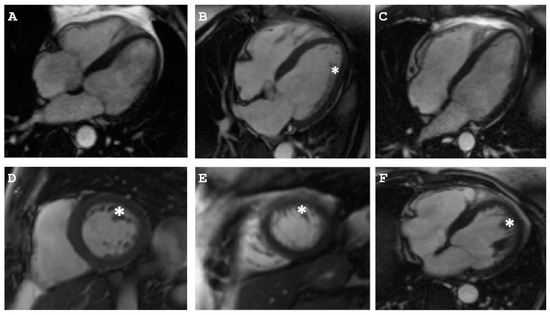

2.1.1. Family A

2.1.2. Family B